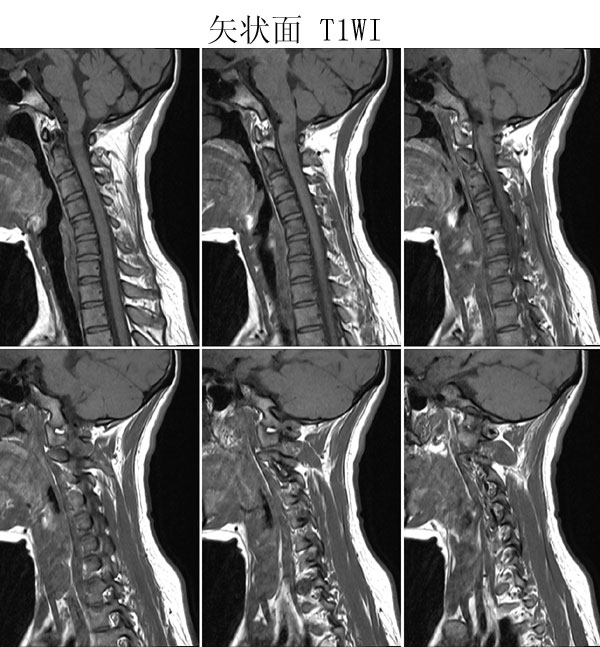

本病例来自广东同江医院

病史:女,27岁,洗头按摩时扭颈导致昏迷,检查发现颈椎占位

手术病理:

神经鞘瘤